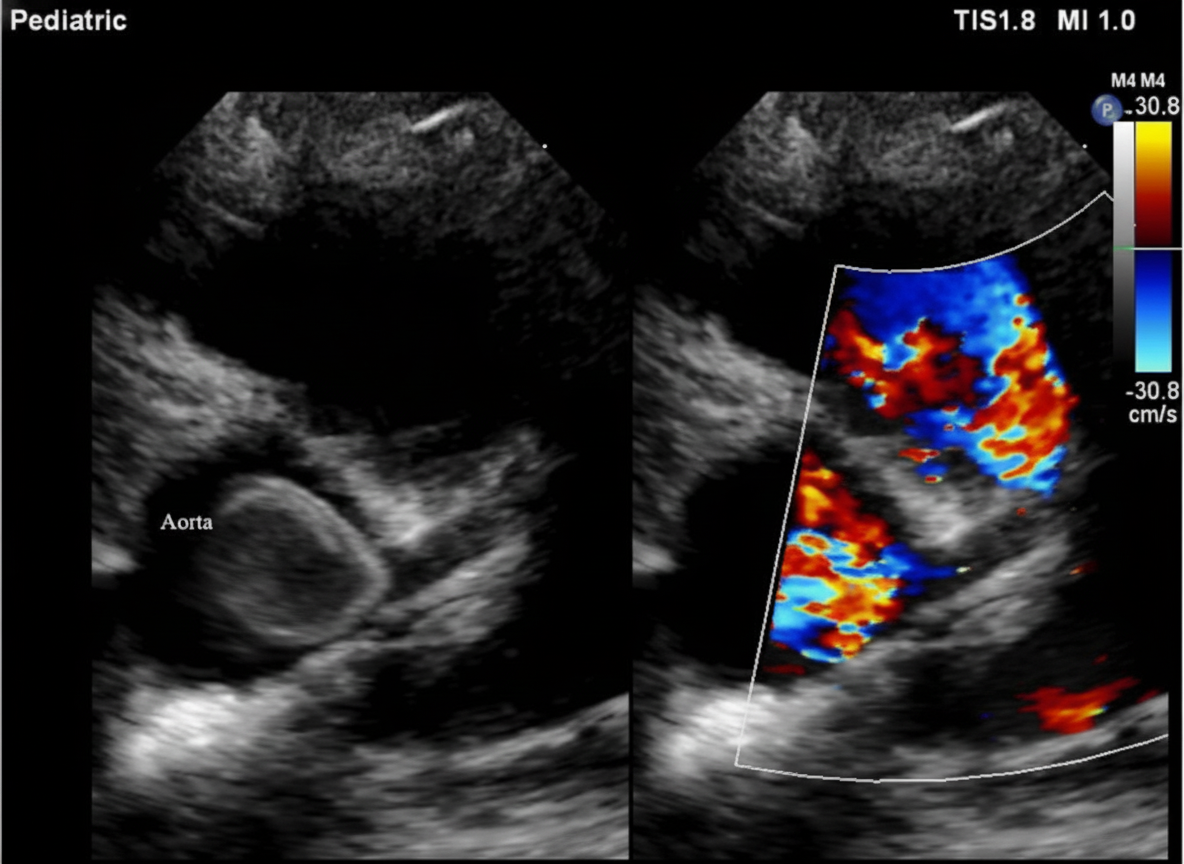

Explanation: ***Ductal-dependent systemic circulation*** - This image depicts a **patent ductus arteriosus (PDA)**, where blood flows from the aorta to the pulmonary artery, creating a left-to-right shunt. - In isolated PDA, the shunt is **left-to-right**, meaning blood flows from the systemic circulation (aorta) to the pulmonary circulation (pulmonary artery). The **systemic circulation is NOT ductal-dependent** in this condition. - **Ductal-dependent systemic circulation** occurs in critical left-sided obstructive lesions such as **critical aortic stenosis, interrupted aortic arch, or hypoplastic left heart syndrome**, where systemic blood flow depends on right-to-left shunting through the ductus arteriosus. - Therefore, this statement is **FALSE** for isolated PDA. *Ibuprofen inhibits Prostaglandin production leading to closure* - **Ibuprofen** and other NSAIDs like indomethacin inhibit **COX enzymes and prostaglandin synthesis**, which is crucial for maintaining the patency of the ductus arteriosus. - Inhibiting prostaglandin production facilitates the **closure of the PDA** in newborns, making this a TRUE statement. *Anatomical closure occurs by 2-3 weeks* - The ductus arteriosus typically undergoes **functional closure** within the first 24-48 hours after birth due to increased oxygen tension and decreased prostaglandins. - **Anatomical closure**, involving tissue remodeling and fibrosis, usually occurs within **2-3 weeks** of life in normal circumstances. - A PDA persisting beyond this period (as in this 6-week-old baby) represents a **persistent/patent ductus arteriosus** requiring intervention. *Left ventricular failure* - A significant **left-to-right shunt** through a PDA increases blood flow to the pulmonary circulation, leading to increased venous return to the left atrium and ventricle. - This increased volume load on the **left ventricle** can eventually lead to **left ventricular dilation and failure** over time if the PDA remains uncorrected, making this a TRUE statement.